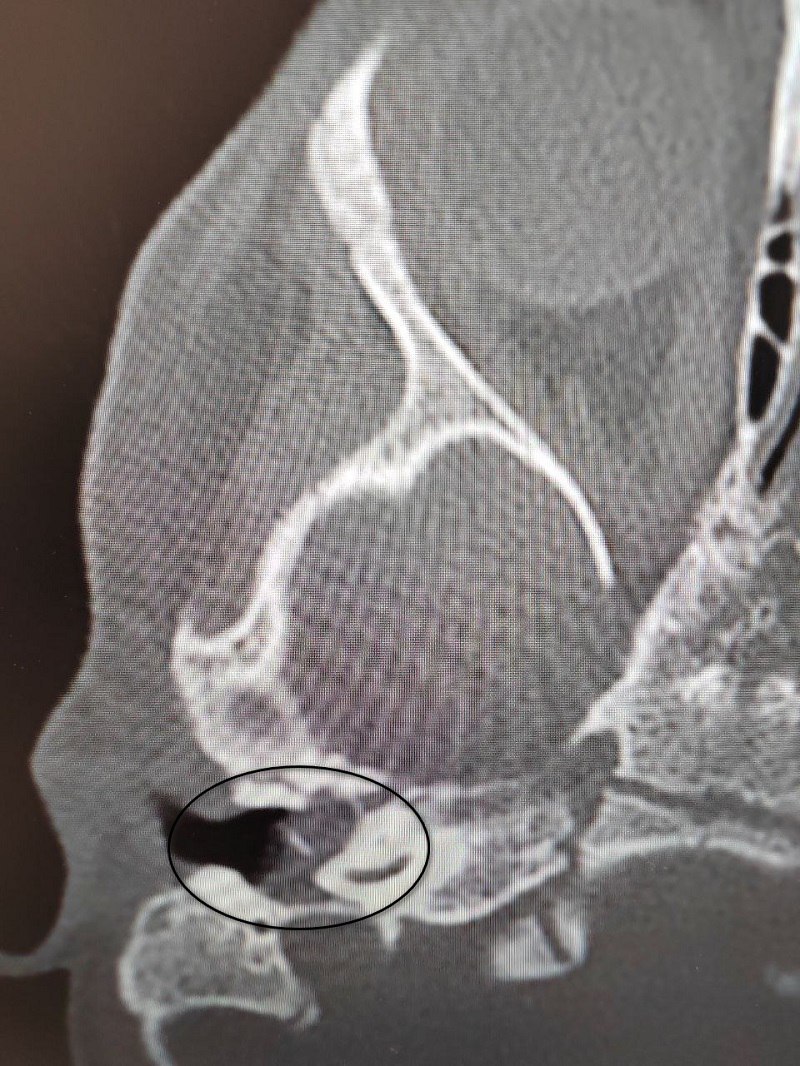

Малышка поступила в ВОДКБ №1 с правосторонним хроническим гнойным средним отитом и подозрением на врождённую холестеатому барабанной полости (кистозное патологическое образование в среднем ухе). Ей грозила потеря слуха.

«Всё началось с обычной ОРВИ, после которой появились боли в ухе. Консервативное лечение не принесло облегчения, и ситуация осложнилась парезом лицевого нерва – он характеризуется слабостью мимических мышц. После обследования был поставлен диагноз – «врождённая холестеатома», – отметили медики.